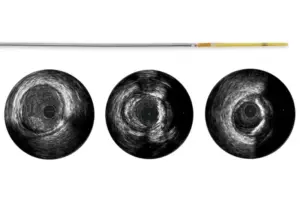

ВСУЗИ

Refinity — Ротационный катетер для ВСУЗИ

Ротационный IVUS-катетер нового поколения Philips Volcano. Частота 45 МГц для максимально чёткого изображения. GlyDx-покрытие, мягкий гибкий кончик. Совместим с радиальным доступом и направляющими катетерами от 5F.